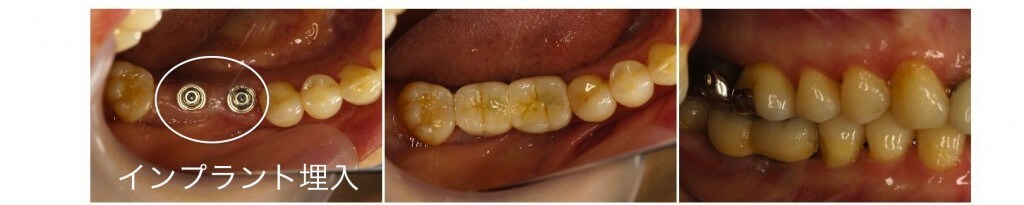

歯根破折により失った下顎の臼歯をインプラントにより修復した症例です。顎の内側に骨の隆起が存在し、この様な場合では義歯による修復は非常に困難でインプラント補綴が有効です。(治療後の写真は治療終了2年経過後の状態です。)